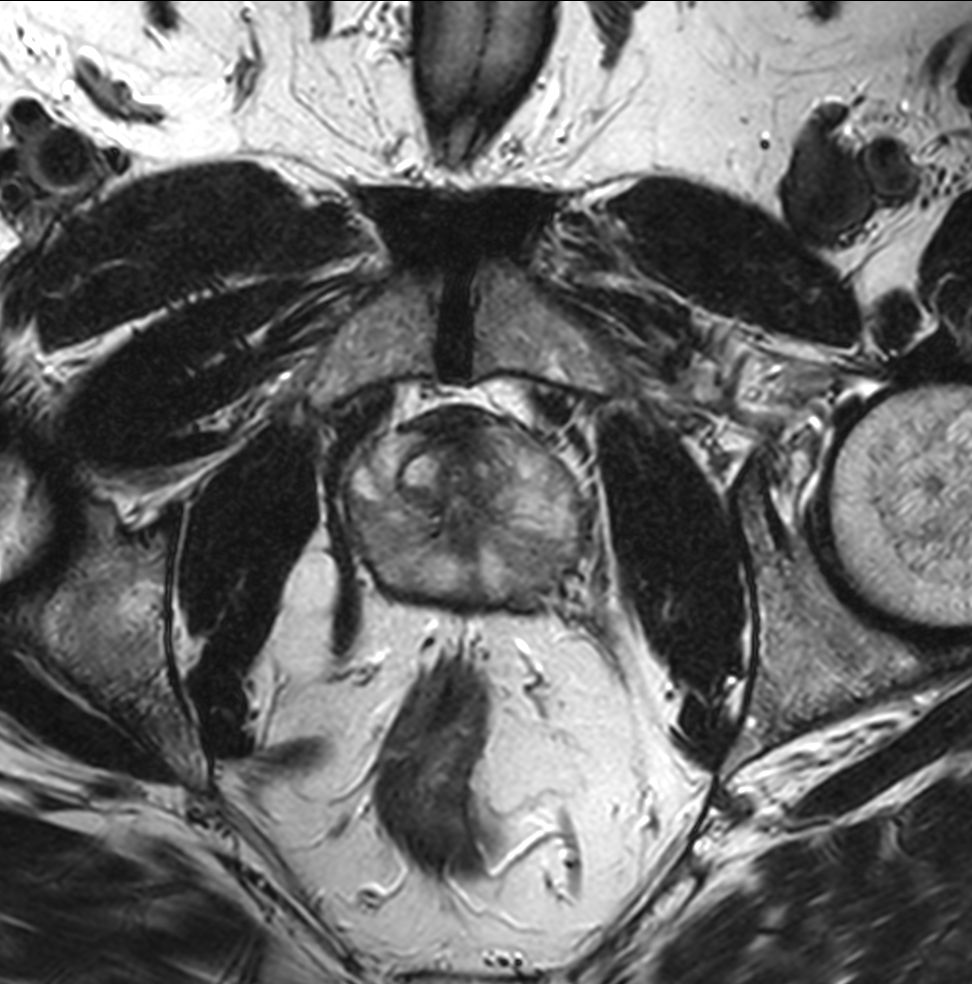

Axial T2w TSE